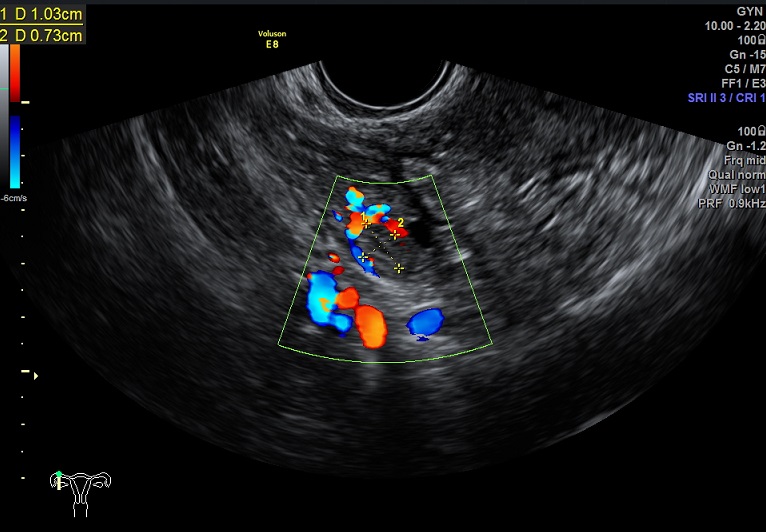

子宫动脉:

L:PSV:34.6cm/s ,舒张早期血流反向

R: PSV:28.8cm/s ,舒张早期血流缺失